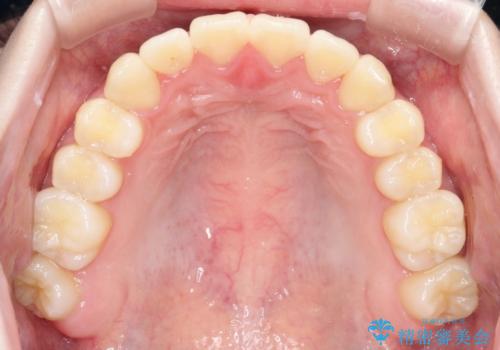

【インビザライン】前歯のガタガタをなおしたい

- 前歯のガタガタを主訴に来院されました。

開咬ぎみであったため、しっかりと前歯が噛むように計画を立てて治療をおこないました。

仕上がりも良く、患者様にも満足していただきました。

インビザラインは前歯を噛ませるような開咬の治療も得意としています。